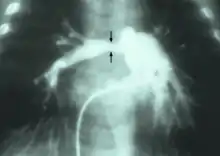

| Stenosis of the right pulmonary artery in a patient which was due to a case of congenital rubella. | |

- Rubella: infection during pregnancy that can lead to heart abnormalities in neonates[5]